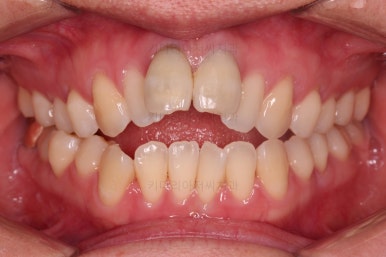

4. 마무리

앞니 임플란트의 색깔, 모양 등으로 몇 번의 수정 작업을 거친 뒤, 치료를 종료합니다.

잇몸뼈의 상태에 비해 매우 양호하게 임플란트가 완성되었고요.

개방교합, 2급 부정교합 등 모든 면에서 개선이 잘 되었습니다.

부산개방교합 전후 비교를 해보겠습니다.

웃을 때 잇몸선이 거의 보이지 않아 잇몸의 레벨이 위에 있었던 점이 완벽히 가려졌고요.

얼굴모습의 변화를 보면 거의 완벽하다 싶을 정도의 치료가 된 것이 아닌가 싶습니다.

앞니의 위치, 교합 개선, 웃는 모습 개선, 입매, 돌출감 개선, 옆선 등등 치료가 매우 고난도였던점을 생각한다면 이보다 더 좋은 교정 + 앞니 임플란트가 없다 싶을 정도의 치료였습니다.

임플란트 완료까지 총 3년 걸렸으며 앞니 제외 추가 발치는 없이 부산개방교합 교정하였습니다.